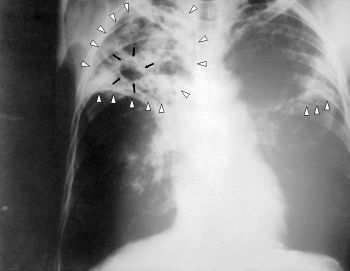

Skjermbilde av tuberkulosepasient.

Foto: US Department of Health and Human Services (1972).